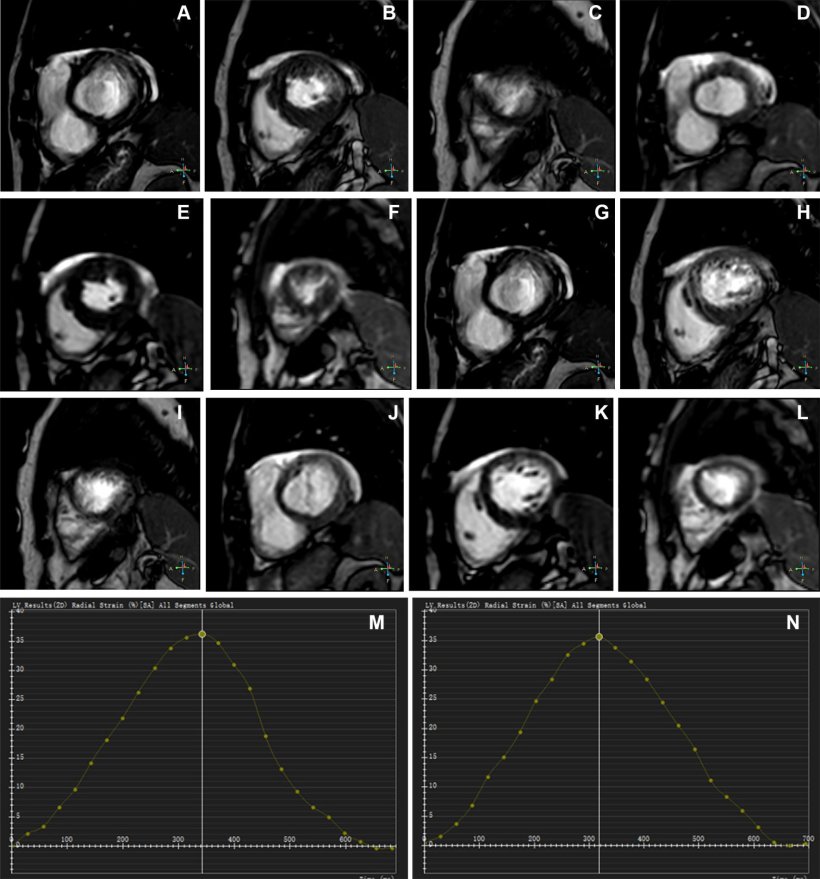

AI-enhanced single-shot cine MRI produces superior image quality and provides ventricular measurements comparable to conventional cine MRI.

The AI-CS single-shot cine demonstrated significantly better image quality compared to conventional cine, particularly in participants with arrhythmia, with fewer mistrigger events and motion artifacts. Mistriggering can occur when a patient has arrhythmia, causing the scanner to miss the intended phase. Motion artifacts in MRI are common image disturbances that can be caused by physiological (breathing, cardiac) or involuntary movement during data acquisition.

AI-CS also showed good-to-excellent agreement with conventional cine for measurements of biventricular volumes and left ventricular mass. In cases where conventional cine failed, AI-CS provided ejection fraction—the measurement of how much blood the heart’s left ventricular pumps out—comparable to values from echocardiography.

“The AI-CS sequence effectively avoided the cardiac motion artifacts commonly caused by mistriggering in conventional cine,” Zhang said. “It also demonstrated a shorter mean acquisition time while providing improved image quality, particularly in the visualization of the endocardial border, epicardial border, papillary muscles and cardiac motion.”

The success rate for the AI-CS single-shot cine sequence in the study was 100% compared to 88% for the conventional cine sequence, underscoring the challenge of using cardiac MRI to accurately assess ventricular function in patients with arrhythmia.